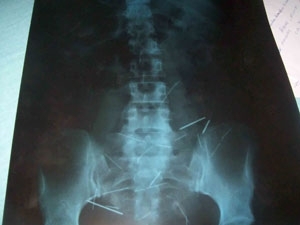

O médico afirmou que a mulher disse que introduzia as agulhas no corpo quando tinha entre 9 e 10 anos. Sua mãe era costureira, por isso ela tinha fácil acesso aos objetos em casa.